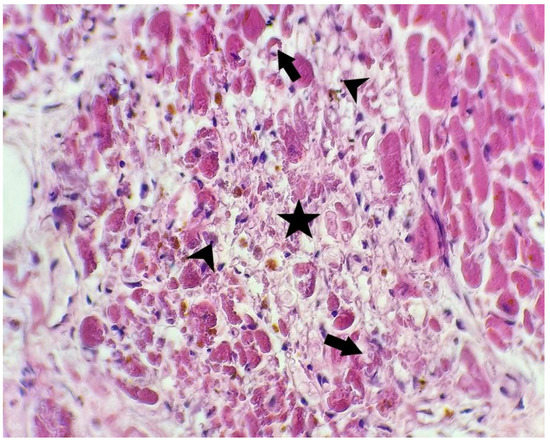

- In one case (with positivity for SARS-CoV-2 antibody), we observed a large area of myocardial necrosis with enucleated muscle fibers, eosinophilia, extravasated erythrocytes, scattered lymphocytes, neutrophils, and necrotic debris, with a halo of granulation tissue composed of newly formed capillaries, macrophages, and lymphocytic infiltrate.

| Case no. 6 | Rich diffuse inflammatory lymphocytic infiltrate in the subepicardial space visceral pericardium, with focal fibrin deposits on the surface Large extended areas of fibrosis interposed between myocardial fibers, sequestrating groups or individual myocytes, with thick, poorly cellularized, horizontally-arranged collagen fibers. In these patches of fibrosis, there is a more myxoid appearance, with an increased number of blood vessels and with a perivascular scattered lymphocytic infiltrate Small, poorly-defined areas of myocardial fibers with cytoplasmic vacuolation, nuclear pyknosis, apoptosis, and necrotic debris between these fibers Undamaged myocytes near the fibrotic patches suffered nuclear enlargement, with irregular borders and granular fine dispersed chromatin, a sign of cellular suffering Severe atherosclerosis of the coronary arteries with secondary subocclusion Large area of myocardial necrosis with enucleated muscle fibers, eosinophilia, extravasated erythrocytes, scattered lymphocytes and neutrophils and necrotic debris, with a halo of granulation tissue composed of newly-formed capillaries, macrophages, and lymphocytic infiltrate |